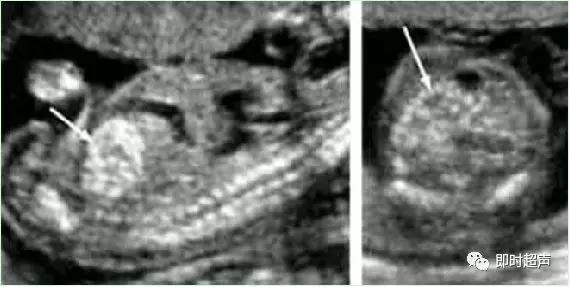

四、脉络丛囊肿(CPC)

脉络丛囊肿CPC 是指孕 14 ~ 28周经超声检查在胎儿侧脑室脉络丛内发现的散在的直径≥2mm 的小囊肿。

脉络丛是脑脊液分泌的重要场所,在胚胎发育的不同时期脉络丛的结构发生较大变化,间充质基质由稀薄逐渐浓缩,脉络丛内的毛细血管发生血管瘤样改变,包裹一部分脑脊液形成脉络丛囊肿。

✔ CPC发生率1%-2%,正常胎儿可一过性出现。

✔ 声像图为在均质强回声的脉络膜丛内见到圆形或椭圆形无回声结构,多为3-5mm大小。

✔ 单纯CPC中染色体异常的机率在1%-2.4%。

✔ 妊娠26-28周左右95%以上的CPC逐渐消失。

✔ 大约有1-3%的正常人群中在中期妊娠的超声检查中可发现有CPC。有建议5mm以下不报告。

✔ 如果囊肿小于1cm或越来越小,染色体异常可能性小。

✔ 囊肿大于 1 cm 时,约 1% ~2%有胎儿染色体异常,这些胎儿大部分都有另外的畸形。以 18 、21-三常见。

✔ 胎儿脉络丛囊肿作为产前超声诊断中的超声标记之一,可以提示胎儿染色体异常的风险性。

✔ 囊肿较大或胎儿合并其他畸形时应做胎儿染色体检查。